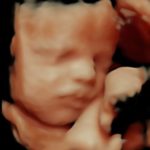

4D/5D/HD Ultrasound Gallery

Gallery